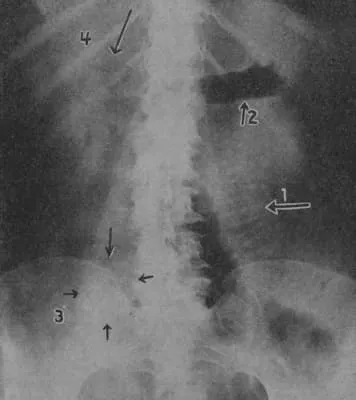

Leo George Rigler was an American radiologist remembered for describing Rigler's sign.